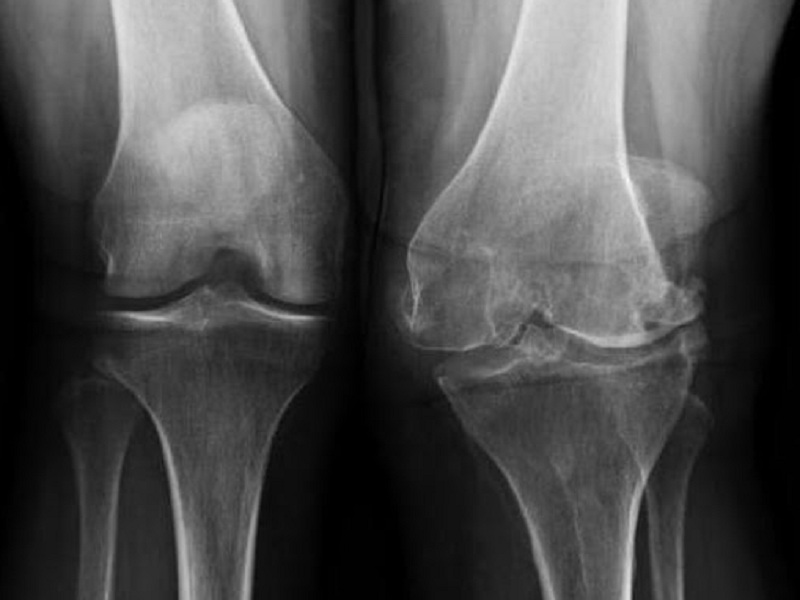

Come è noto, la gonartrosi si associa ad un bisogno insoddisfatto di trattamenti sicuri ed efficaci che modifichino i sintomi e la malattia.

Gli studi clinici finora condotti hanno documentato la capacità di questo farmaco sperimentale di migliorare i risultati riferiti dai pazienti (PRO) e di mantenere l’ampiezza dello spazio articolare mediale (JSW) radiografico rispetto al placebo (PBO), insieme ad un buon profilo di safety.

L’analisi ha incluso 276 pazienti con un’età media di 61 ± 8,2 anni e un BMI di 31,8 ± 4,9 kg/m2. La coorte era composta per il 62,7% da donne, con il 45,3% che presentava un grado di Kellgren-Lawrence pari a 3 e un’ampiezza dello spazio articolare mediale di 2,63 ± 0,69 m. Circa i due terzi della coorte erano bilateralmente sintomatici.